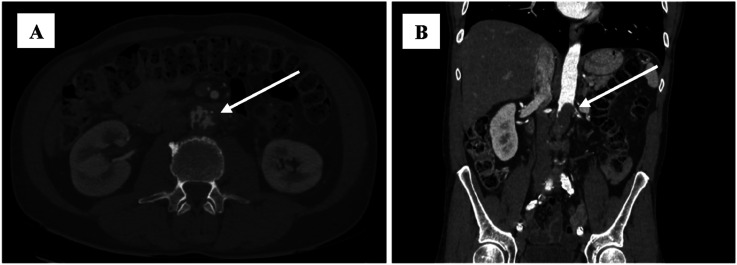

摘要:原发性主动脉恶性肿瘤是一种非常罕见的病理,迄今为止文献中仅报道了190例主动脉肿瘤。通常,症状是隐匿的和非特异性的,所以这种疾病在晚期才被诊断出来。目的:在此,我们报告一例原发性主动脉恶性肿瘤。在我们的病例中,诊断是通过计算机断层血管造影(CTA)和在主动脉造影中获得的不确定肿块的活检来建立的。方法:患者手术切除病变主动脉段并合并肿瘤。组织病理检查显示为原发性主动脉恶性肿瘤-血管肉瘤。术后患者按肉瘤标准治疗方案接受辅助化疗。结果:术后1个月行胸腹骨盆CT检查,未见病灶转移及病理淋巴结。结论:手术联合全身治疗可提高总生存率。

Introduction: Primary aortic malignancy is a very rare pathology, with only 190 cases of aortic tumors reported in the literature to date. Usually, symptoms are insidious and nonspecific, so the disease is diagnosed at an advanced stage. Objective: Here, we present a case report of a primary malignant tumor of the aorta. In our case, the diagnosis was established using computed tomography angiography (CTA) and biopsy of indeterminate masses obtained during aortography. Methods: The patient underwent surgical resection of the affected aortic segment along with a tumor. Histopathological examination revealed the diagnosis of a primary malignant tumor of the aorta - angiosarcoma. Postoperatively, patient received adjuvant chemotherapy according to the standard treatment regimen for sarcoma. Results: One month later, postoperative CT of a chest, abdomen and pelvis was performed, revealing no evidence of metastases or pathological lymph nodes in the examined areas. Conclusion: Combined surgical and systemic therapies may improve overall survival.